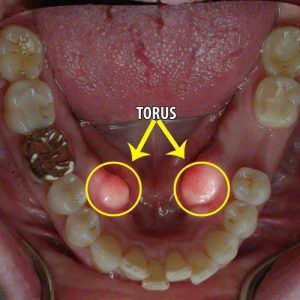

2. TORUS HÀM DƯỚI

Ở VN tỉ lệ dân số mắc torus hàm dưới có tỷ lệ thấp chiếm 3,6% dân số. Tỉ lệ này ở nam (4,8%) nhiều hơn nữ (3%). Hơn nữa nam vừa có torus khẩu cái vừa có torus hàm dưới với tỷ lệ cao gấp đôi nữ.

Đối với torus hàm dưới, vị trí thường gặp nhất là vị trí ở mặt lưỡi đối diện với vùng răng cối nhỏ. Torus hàm dưới thường gặp nhất là ở hai bên, đối xứng nhau. Và trường hợp torus 1 bên cũng không phải hiếm.